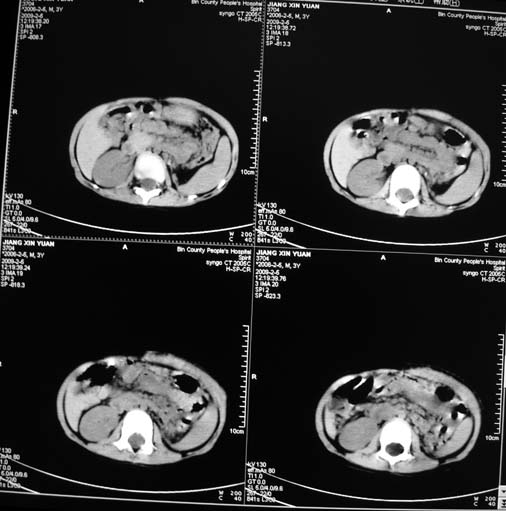

男,3岁,肾母细胞瘤术后,肝脏的低密度是什么?

胰尾下方见两枚囊形灶,肠管?病灶?左侧肾上腺区见团块状影,转移病灶?术后表现?建议与前片对比,肝脏病灶好像有牛眼表现,不除外转移,如果不增强,建议加做个b超,至少可分清其囊性或者实性,又便宜,免费自已给他弄一下也行,对诊断有帮助

左肾母细胞瘤术后,多发性转移可能性大。

左肾母细胞瘤术后:肝脏多发低密度灶,考虑转移可能性大。

左肾母细胞瘤术后:肝脏多发低密度灶,考虑转移可能.请结合临床及增强以及术前检查等